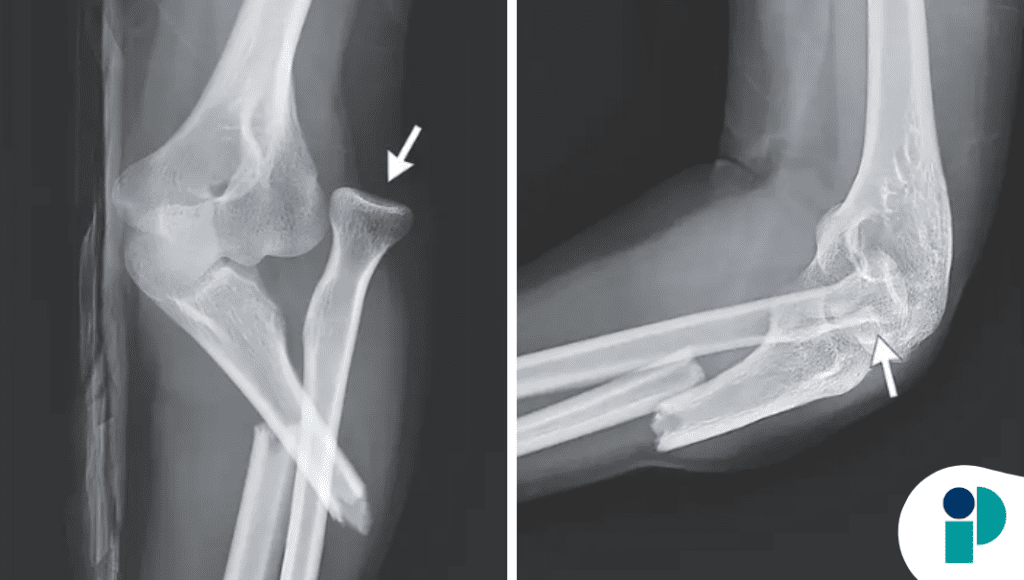

Aunque inicialmente la lesión parecía rutinaria, los estudios de imagen revelaron el hallazgo clave: fractura del tercio proximal del cúbito asociada a luxación de la cabeza radial, compatible con una fractura de Monteggia, una lesión combinada que puede pasar desapercibida.

Este tipo de fractura es particularmente desafiante porque la fractura del cúbito suele ser evidente, pero la luxación radial puede ser sutil y fácilmente omitida, especialmente en adultos, donde es menos frecuente. La falta de reconocimiento oportuno puede llevar a inestabilidad crónica del codo, limitación funcional e incluso lesión nerviosa.